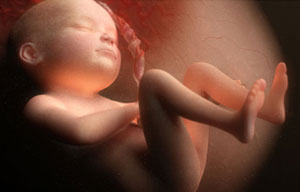

Ребенок продолжает расти, хотя все органы и системы уже сформировались, легкие ждут своего времени, чтобы принять первый воздух после рождения. Пока ребенок в лоне матери дышит и питается с помощью плаценты и пуповины. Малыш получает питательные вещества и кислород через две артерии и вену, которые переплетаются в пуповину. Поэтому после родов ждут, пока пуповина перестанет пульсировать и только потом ее перерезают.

Питание (кислород и питательные вещества) ребенок все еще получает через плаценту мамы.